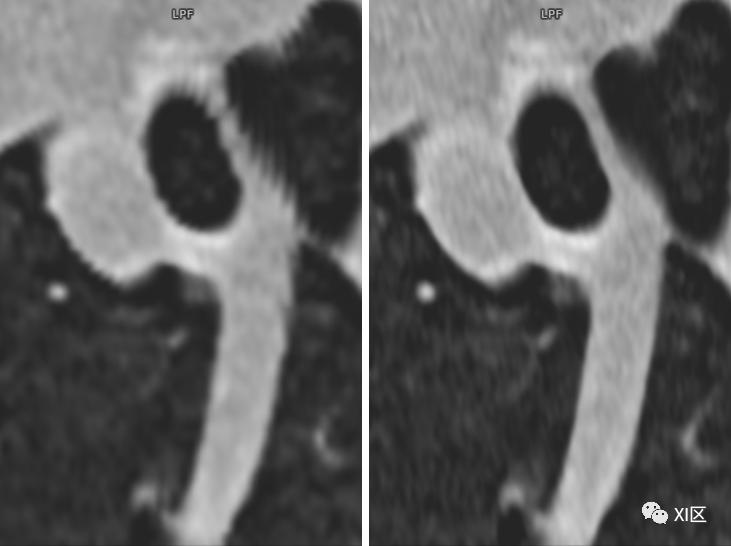

SOMATOM Force CT常规重建0.6 mm(192x0.6 mm)图像(左)与IVR重建0.6 mm(576x0.6 mm)图像(右)比较。使用IVR技术的图像肺内支气管细微结构显示更清晰。

SOMATOM Force CT常规重建0.75 mm图像(左)、0.6 mm(192x0.6 mm)图像(中)与IVR重建0.6 mm(576x0.6 mm)图像(右)比较。使用IVR技术的图像肺内支气管细微结构及肺大泡显示更清晰。